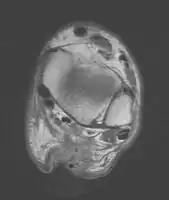

MRI can be used to discern incomplete ruptures from degeneration of the Achilles tendon, and MRI can also distinguish between paratenonitis, tendinosis, and bursitis. This technique uses a strong uniform magnetic field to align millions of protons running through the body. These protons are then bombarded with radio waves that knock some of them out of alignment. When these protons return they emit their own unique radio waves that can be analysed by a computer in 3D to create sharp cross sectional image of the area of interest. MRI can provide unparalleled contrast in soft tissue for an extremely high quality photograph making it easy for technicians to spot tears and other injuries.

Transverse plane/Achilles tendon rupture -